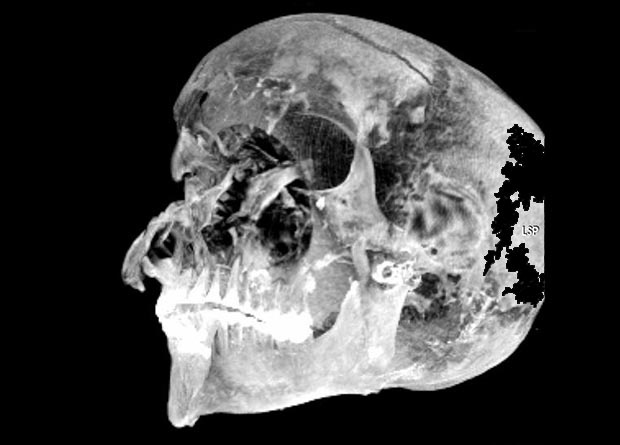

Ученые провели КТ-сканирование мумии фараона Секененра Таа II, стоявшего у истоков возрождения Египта после эпохи владычества гиксосов. Изучение множественных повреждений головы, положения рук и характера бальзамирования позволило реконструировать подробности его насильственной смерти и подтвердить, что египетский правитель погиб, попав в руки врагов. Результаты исследования опубликованы в журнале Frontiers in Medicine.